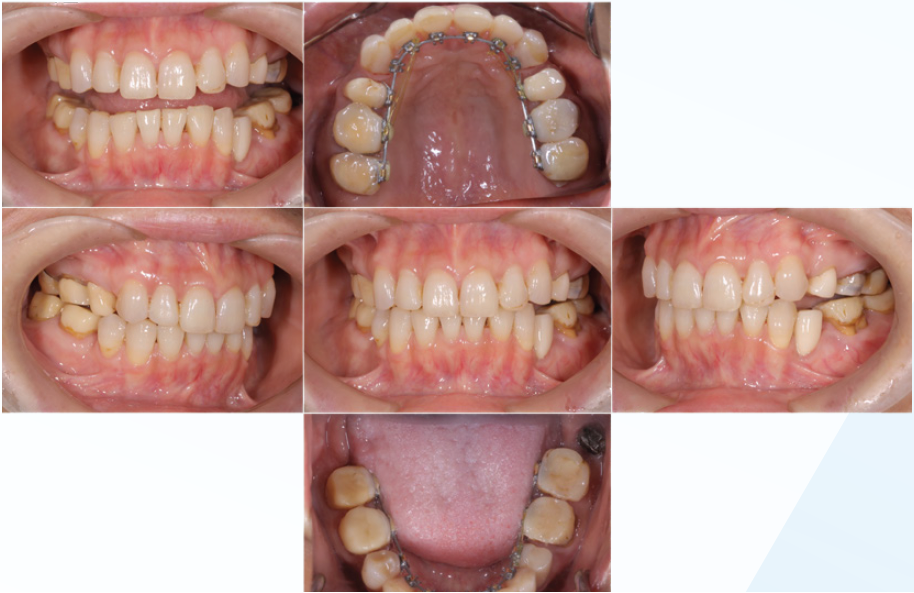

「臼歯部に限局して失活歯が存在し、多発性の根尖病変が認められる症例」

左下大臼歯部の急性炎症を主訴に来院(図16・17・18)。

緊急処置を行い、基礎資料を収集し問題点を抽出し、総合診断治療計画を立案し、患者に説明した。臼歯部に歯科治療が繰り返されている原因の一つに咬頭嵌合位が安定せず、咬合干渉が認められる病的咬合が挙げられる(図19)。臼歯部に応力が集中し、補綴装置やセメントが安定せず歯冠部からの漏洩によって根管内が感染していることも予測できる。包括的な見地から、咬合治療を行うために矯正治療の必要性を説明し承諾を得た。

矯正的診断は上下顎骨劣成長と骨格性開咬を伴うAngleⅡ級症例。矯正治療の目的は前歯の叢生の改善と適正な被蓋関係の確立。治療計画は上顎両側第一小臼歯を抜歯し、上顎前歯の叢生の改善と下顎両側第二小臼歯を抜歯し、下顎両側大臼歯を近心移動し、咬合高径を調整し前歯部の被蓋関係を改善する。初期治療にて炎症のコントロール、主に感染根管の再治療を行い(図20)、矯正治療に入る(図21)。矯正治療により歯のポジションが改善した後、プロビジョナルレストレーションにてリハビリテーションを検証し(図22)、最終補綴処置を行う(図23)。臼歯部の環境が改善された事で、臼歯への力の集中による失活歯の歯根破折の可能性の減少と根尖周囲の歯周組織の安定を確立できた。

<緊急処置後、初期治療前の口腔内写真と14枚法>

歯周病の程度は軽度。前歯部開口咬合状態を呈し、

既往歴はほぼ臼歯部に集中している

口腔内の傾向から臼歯に過度な負担があり、

さまざまな病態に至っていると推測する

(図19-1)

(図19-2)

(図21)

咬合治療によって臼歯に過度な負担がかからないように

治療咬合を付与するための準備として全顎的矯正治療を行う